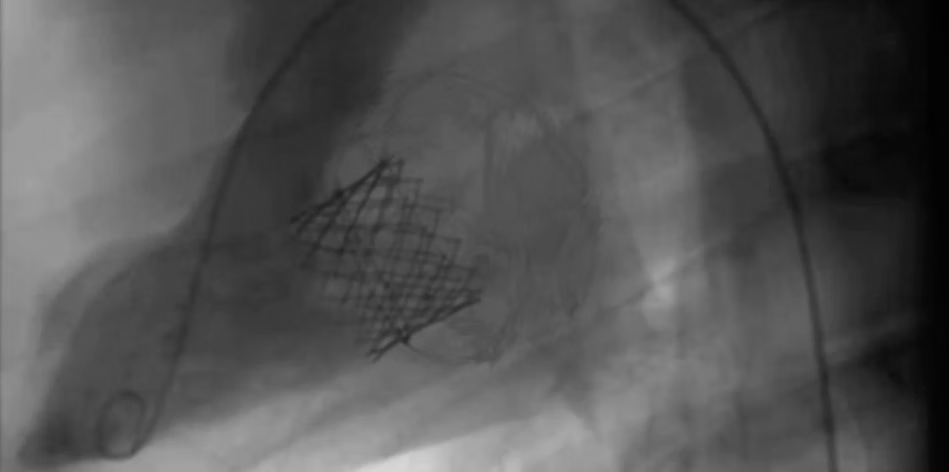

TruLeaf has performed a successful first-in-human study for tricuspid valve replacement at the end of 2025. We are currently enrolling new patients.